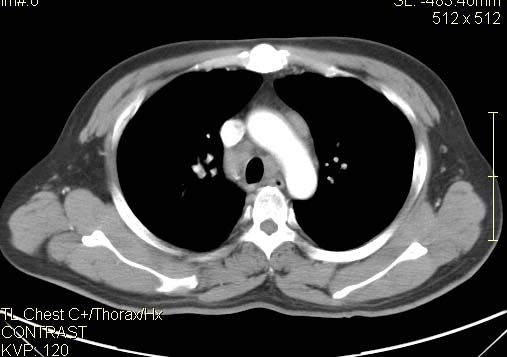

以下是引用qc80012345在2007-4-17 12:33:00的发言:[br]右肺下叶周围型肺癌伴肺门及纵隔内淋巴结转移;比较清楚。

以下是引用qingyuan在2007-4-17 14:19:00的发言:[br]右肺下叶外侧后段胸膜下区节结样病变、分叶、内可见空洞,壁厚薄不均,胸膜凹陷、肺门周围区纹理增粗、僵硬、并近似小结节样改变,肺门区软组织节结、纵膈淋巴结肿大,患者病史长、抗炎治疗无好转炎性改变基本排除,考虑:右肺下叶周围型肺癌伴纵膈及右肺门区淋巴结转移、肺内淋巴管受侵。